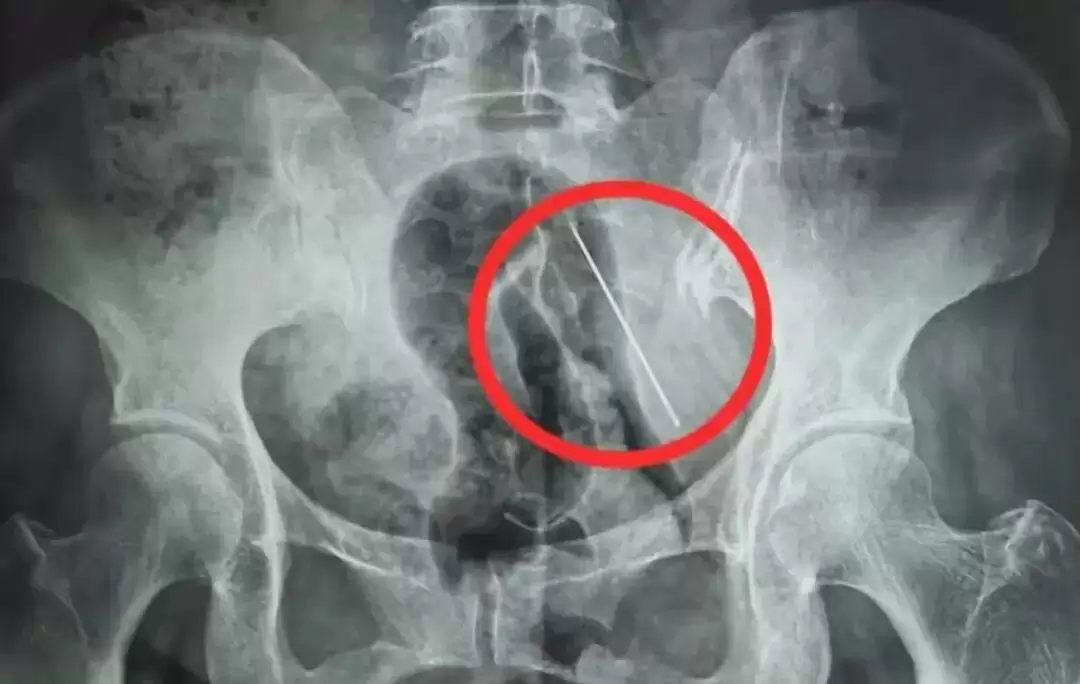

X光片显示张某腹部内有异物(医院供图)

接诊后,急诊科当即安排张某进行腹部CT和X线检查。检查结果显示,她的腹壁内有一根长4厘米的异物。经研判,这根缝衣针只是扎入脂肪层内,并未穿透掉入腹腔。

根据病情,张某被转入普通外科进行急诊手术。主治医师赵伟采用了C型臂透视定位技术,在透视引导下,精准找到缝衣针所在位置,手术十分顺利。赵伟表示,由于张某腹部脂肪层较厚,缝衣针并未穿透进入腹腔,避免了腹腔内器官受损的风险,也大大降低了手术难度和术后并发症的可能。